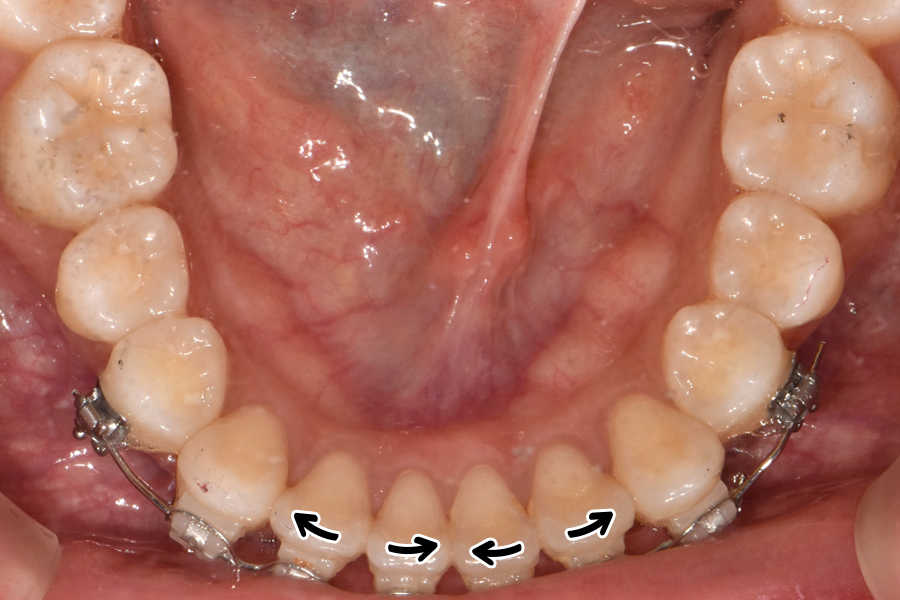

윗니를 보시면 치아 위치가 많이 틀어진 것을 볼 수 있는데요. 아래쪽 같은 경우 비교적 윗니보다 낫지만 그래도 한 쪽 치아가 좀 많이 튀어나와 있고 전체적인 악궁 형태가 조금 찌그러져 있는 것을 볼 수 있습니다.

처음에는 삐뚤었던 치아 배열을 사진상 표시도니 것처럼 화살표 방향으로 돌리는 것을 볼 수 있는데, 클리피씨 교정 같은 경우에는 좀 더 장치가 크고 비용도 기타 장치에 비해 조금 더 비싸지만 그만큼 치아를 더 정밀하게 잡을 수 있다는 장점이 있습니다.